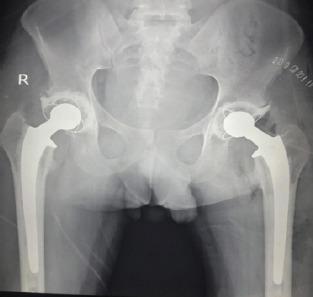

A 28-year-old male student presented with history of acute pain in right hip and inability to walk after a squatting event. He was diagnosed to have osteonecrosis of bilateral femoral head 1 year back, for which he denied further treatment. On clinical examination, right hip examination was painful with flexion, adduction, and external rotation deformity. Radiological examination revealed fracture at subcapital region in neck of right femur with osteonecrosis of femoral head. After discussing treatment options with the patient, we performed total hip arthroplasty (THA). Harris hip scores improved from 17.1 to 83.5.

一名28岁男性学生,在一次蹲起活动后出现右髋急性疼痛和无法行走的病史。他于1年前被诊断为双侧股骨头坏死,他拒绝进一步治疗。临床检查时,右髋检查在屈曲、内收和外旋时疼痛且有畸形。影像学检查显示右股骨颈头下区域骨折伴股骨头坏死。在与患者讨论治疗方案后,我们进行了全髋关节置换术(THA)。Harris髋关节评分从17.1提高到了83.5。